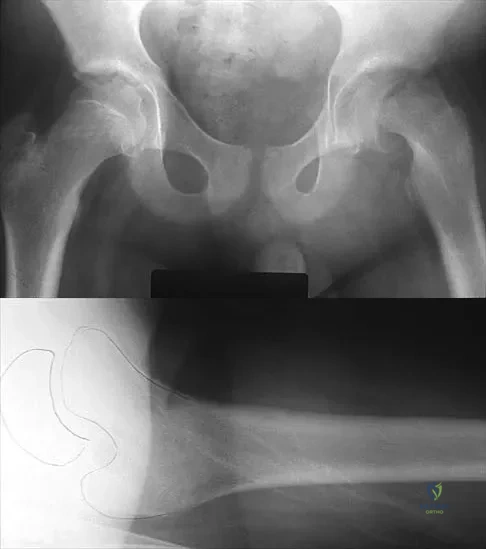

A 57-year-old man with type I diabetes mellitus has had a tender, erythematous right sternoclavicular joint for the past 2 weeks. Radiographs reveal mild osteolysis without arthritic changes, within normal limits. Management should consist of